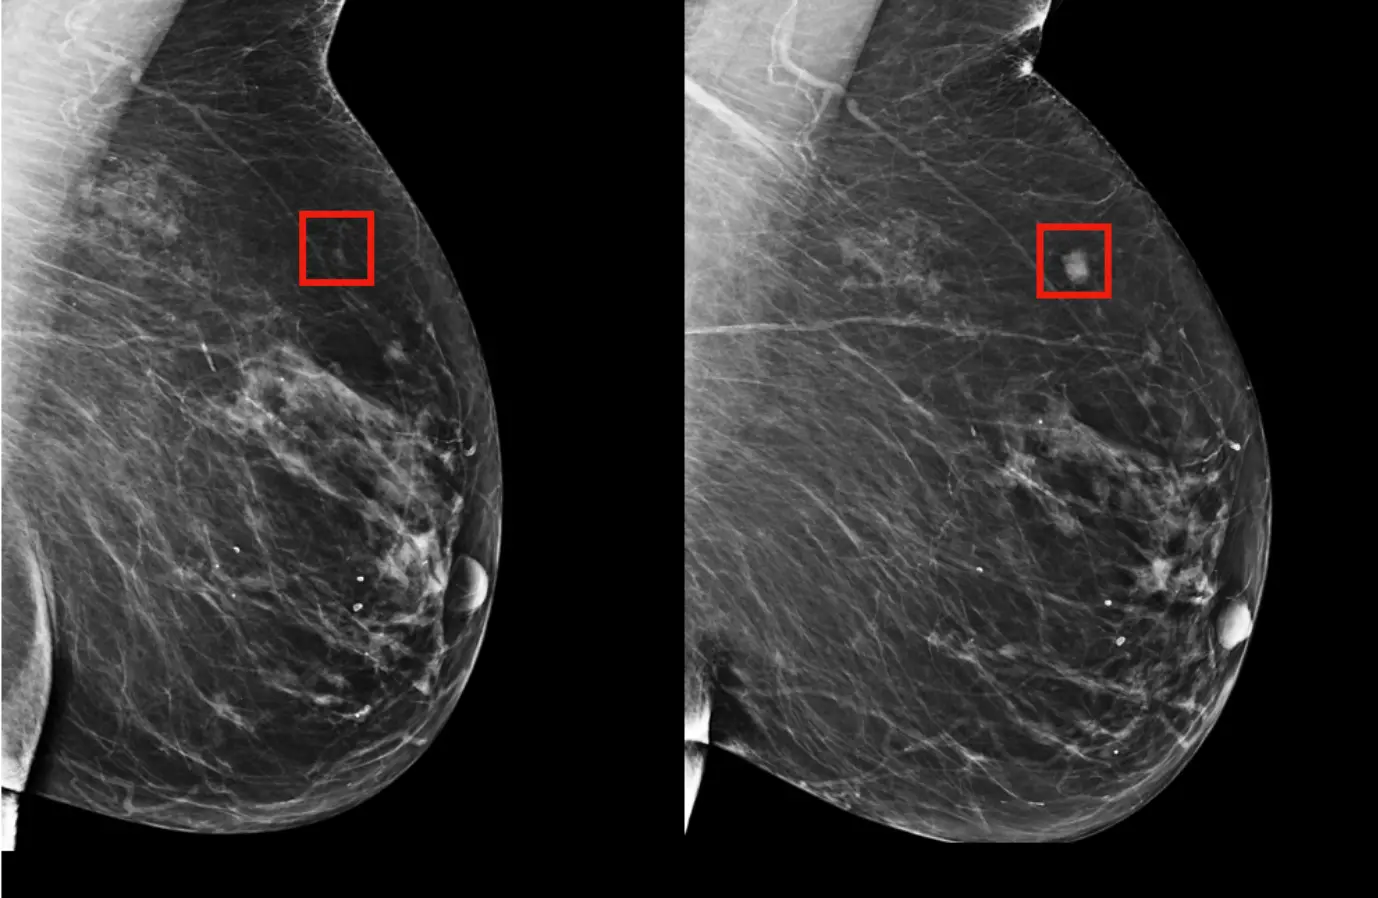

- Medicine: AI models can help generate images for medical research, such as simulating cellular structures or even visualising the potential outcomes of medical procedures.

Predicting future iterations of an image (into a cancerous phase, is another approach to leveraging predictive image models)